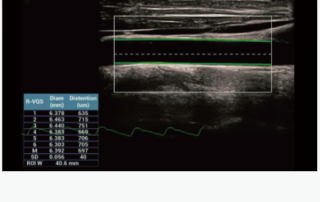

Mindray Ultrasound Consona N9

صور متعلقة